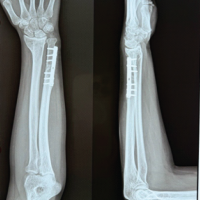

The patient had an uneventful post-operative course and was discharged on day 1 postoperatively after controlling pain and ensuring an intact neurovascular function with immediate range of motion exercises. The patient was in a splint for 2 weeks and then was seen in the office. The incision was well healed, and the patient remained neurovascularly intact. She was NWB for 6 weeks after surgery and advanced to progressive weight bearing as tolerated (Fig. 3).

Figure 3: (a) Anterior-posterior X-ray of the humerus 2 weeks postoperatively, (b) Lateral X-ray of the humerus 2 weeks postoperatively.

The patient was then seen in the office at 3-months postoperatively and reported significant improvement in pain, her elbow range of motion was 0–135° (Fig. 4).

Figure 4: (a) Anterior-posterior AP X-ray of the humerus 3 months postoperatively, (b) Lateral X-ray of the humerus 3 months postoperatively.